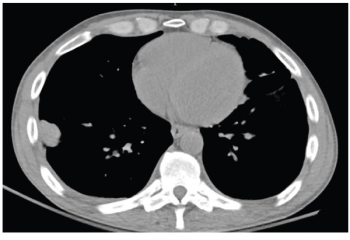

A patient presented with a history of uncontrolled HIV and a history of polysubstance use.

Clinically, C kroppenstedtii has been isolated largely from female subjects, with most samples resulting from breast tissue and the remainder identified in blood, sputum, lung, and prosthetic valve infections.